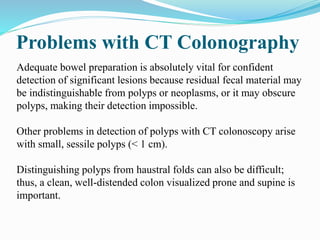

This document discusses colorectal polyps. It defines polyps and describes their types, including neoplastic and non-neoplastic polyps. It discusses adenomatous polyps in depth, noting their malignant potential increases with size over 1cm and villous architecture. Radiological diagnostic methods for polyps including single and double contrast barium enema and CT colonography are explained. The document provides an overview of polyp pathogenesis and genetic syndromes like FAP that increase cancer risk.